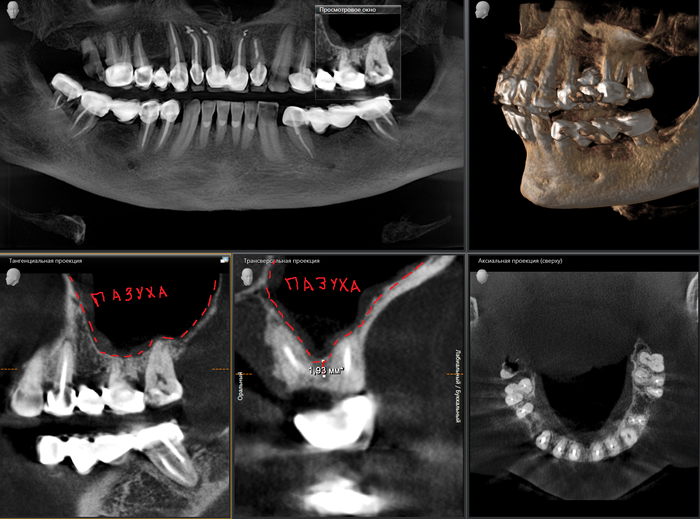

Помните, я говорил, что имплантат должен стоять по центру? Так вот 3-х корневой зуб не исключение. Имплантат устанавливается, как и в предыдущем случае, в перегородку, но уже трехкорневого зуба. Как мы видим высота кости в этой области около 3мм. Данного объема недостаточно для постановки имплантата оптимальной длины, следовательно объем нужно увеличивать. Манипуляцию проводят при помощи специального «костного материала». Кто-то называет его «костный порошок», не путать с «белым порошком», хотя он и белый, но представлен все-таки в виде гранул. Выпускается как просто в стеклянной таре,

Как мы видим условия в данном случае несколько хуже около 2мм. Но это не помешало нам провести операцию в полном объеме.